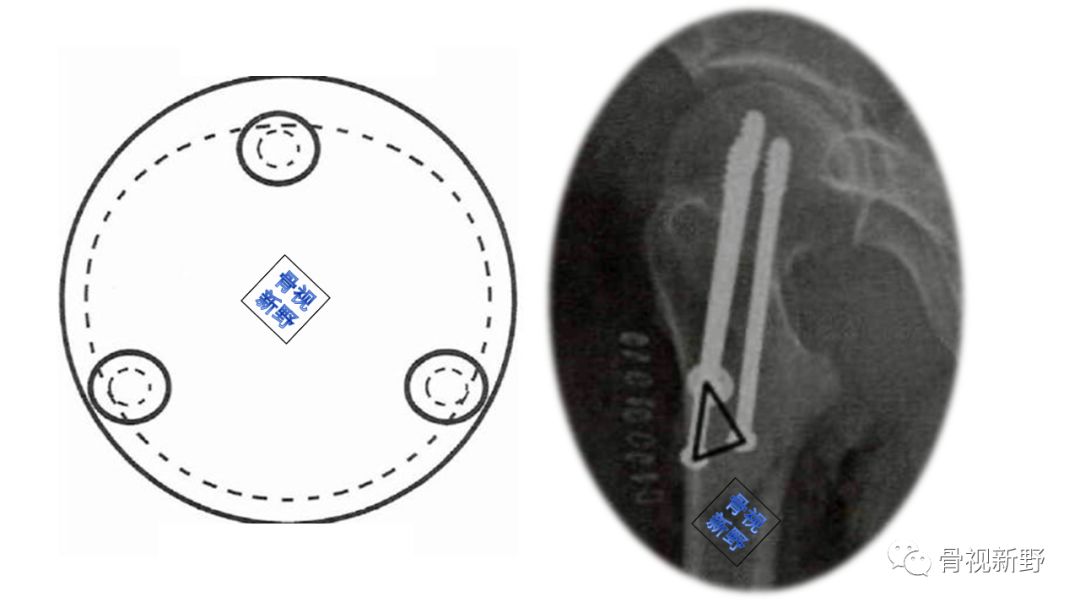

传统固定理念——正三角平行空心钉(Triangle configuration in parallel with the neck)

平行置钉、滑动加压。

贴边固定,通过骨皮质,对骨质疏松者稳定性尤其重要(下图示):

优 点:两枚螺钉靠近骨质坚硬的股骨矩,固定较牢固,可有效对抗股骨颈内侧的压应力,防止退钉。

缺 陷:A.由于股骨颈上宽下窄,正三角固定时螺钉间距小,应力相对集中,会增加转子下骨折的发生概率。因此,正三角形固定应避免在小转子以下进钉。

B.仅靠一枚螺钉固定张力侧骨小梁,抗剪切能力较弱。

传统固定理念——倒三角平行空心钉(Inverted triangle configuration in parallel with the neck)

是目前最常见的内固定方式。

平行置钉、滑动加压(同正三角)。

贴边固定通过骨皮质,对骨质疏松者尤其稳定(下图示):

优 点:

A. 倒三角增强了对股骨颈外侧张应力的抵抗,能耐受更高的垂直负荷,力学稳定性更佳。

B. 倒三角固定更符合股骨近端上宽下窄的解剖特点,置钉较为容易,且三枚螺钉分散,更有利于局部的生物力学固定。

缺 点:倒三角固定时,上方的两枚螺钉会破坏股骨头的血供,从而增加股骨头坏死的风险。